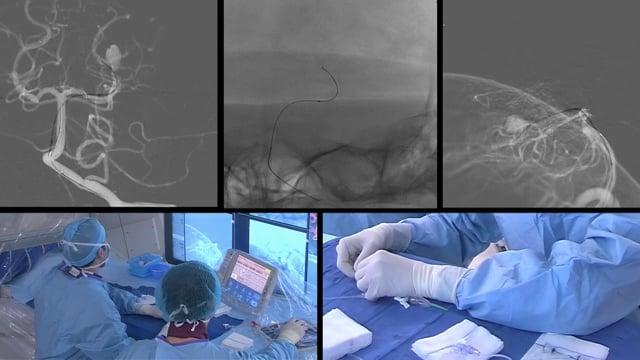

One&Done technique with optiMAX large volume coil